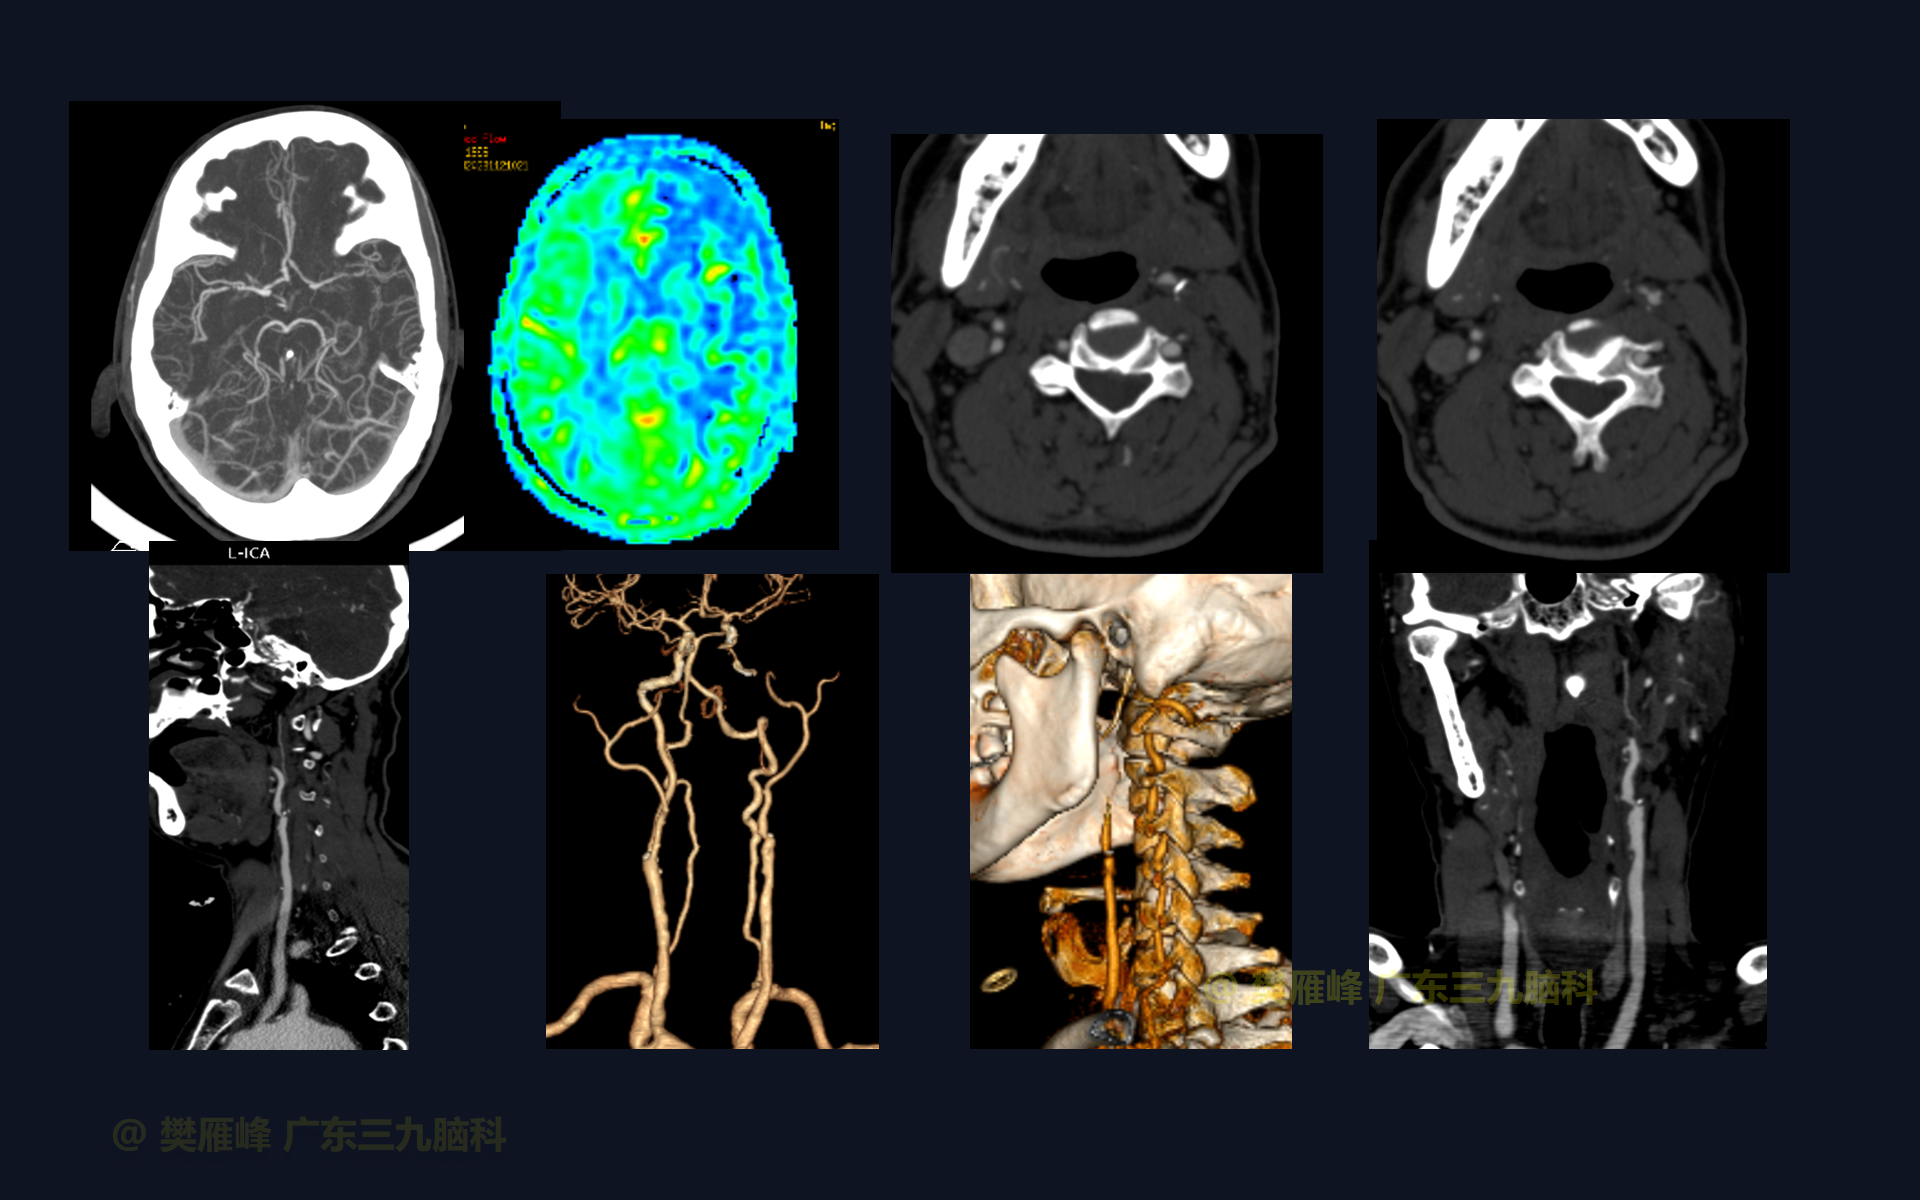

在这个二维手术视频中,展示了一种颈动脉内膜剥脱术开通短期闭塞的颈内动脉的方法。患者是一名67岁的男性,有3月的右侧肢体乏力伴有言语不清,头颅CTA示:左侧颈总动脉上段管腔局限性狭窄(狭窄度约为63%);右侧颈内动脉起始部管壁混合性斑块形成(狭窄度约为70.8%)给双抗血小板保守治疗,3月后复查头颅DSA示左侧颈内动脉闭塞。经术前充分评估,他接受了颈动脉内膜剥脱术,术中穿刺颈内动脉远端有回血,压力不高,在电生理监测下行颈内动脉和颈外动脉内膜剥脱,术中造影均通畅。术后未出现脑梗死和高灌注损伤。术后神经影像学显示血管血流通畅,脑灌注改善。我们展示了颈动脉内膜剥脱术开通短期闭塞的颈内动脉技术要点,及精准的围手术期管理办法。

在这段手术视频中,展示了一名67岁男性的病例,他因右侧肢体乏力伴有言语不清3月余发现的右侧颈内动脉闭塞。